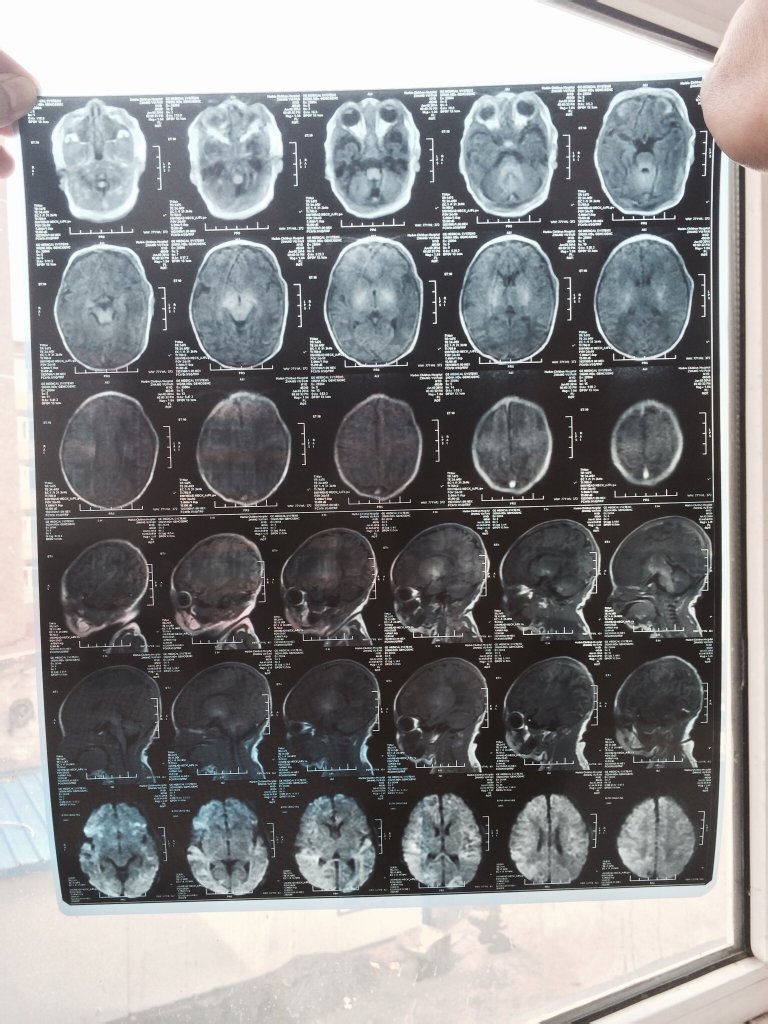

30号宝宝出生,我是顺产,产程2个小时孩子下生后窒息十分钟左右抢救过来,但脑部有水肿,之后24小时里不爱吃奶,31号下午开始伴随右半身抽搐,头向后仰,31号晚上转院查出宝宝是缺氧缺血性脑病和脑白质损伤,现在正在医院治疗,大夫说满月后如果还是有脑白质的话宝宝就一定会有后遗症,孩子现在也就一周左右,我想问下宝宝这么小恢复的几率大吗?留下后遗症的几率会是多少?有像我这种案例宝宝最后完全恢复健康的吗?几率是多少?